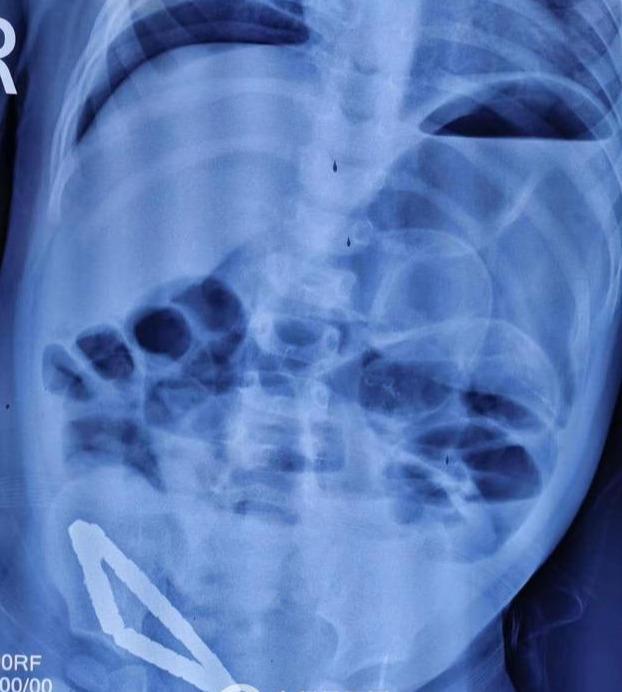

“孩子送到醫(yī)院后,精神萎靡,腹脹明顯,高燒39度,徐州市兒童醫(yī)院普外一科主任曹慧介紹說,由于孩子在當(dāng)?shù)蒯t(yī)院已經(jīng)檢查完善,我們看到檢查報(bào)告后,緊急擬定手術(shù)方案,立即安排手術(shù)。術(shù)中發(fā)現(xiàn)31個(gè)直徑幾毫米的小珠子串聯(lián)成一個(gè)三角形的形狀臥在小腸處,因?yàn)檫@種磁力珠吸力特別大,將患兒小腸緊緊'夾'住,造成患兒三處腸壞死和腸穿孔。深夜奮戰(zhàn)幾個(gè)小時(shí)最終我們將患兒體內(nèi)的31顆磁力珠全部取出,并截掉壞死小腸20cm左右,清理了腹腔的污染物,術(shù)后經(jīng)過一個(gè)星期治療,孩子可痊愈出院,但是小寶貝也遭了不少罪。”

最近僅僅是2個(gè)月的時(shí)間,徐州市兒童醫(yī)院普外科就已經(jīng)接診了好幾例誤食磁力珠的孩子,上述病例的患兒是目前誤食最多的,有31顆,幸好磁力珠都移動(dòng)在小腸相近位置,不然手術(shù)會(huì)更麻煩。而且有些磁珠吃下去時(shí)間長了 ,造成腸穿孔,就要手術(shù)切掉壞死的部分,對(duì)孩子造成嚴(yán)重的傷害。